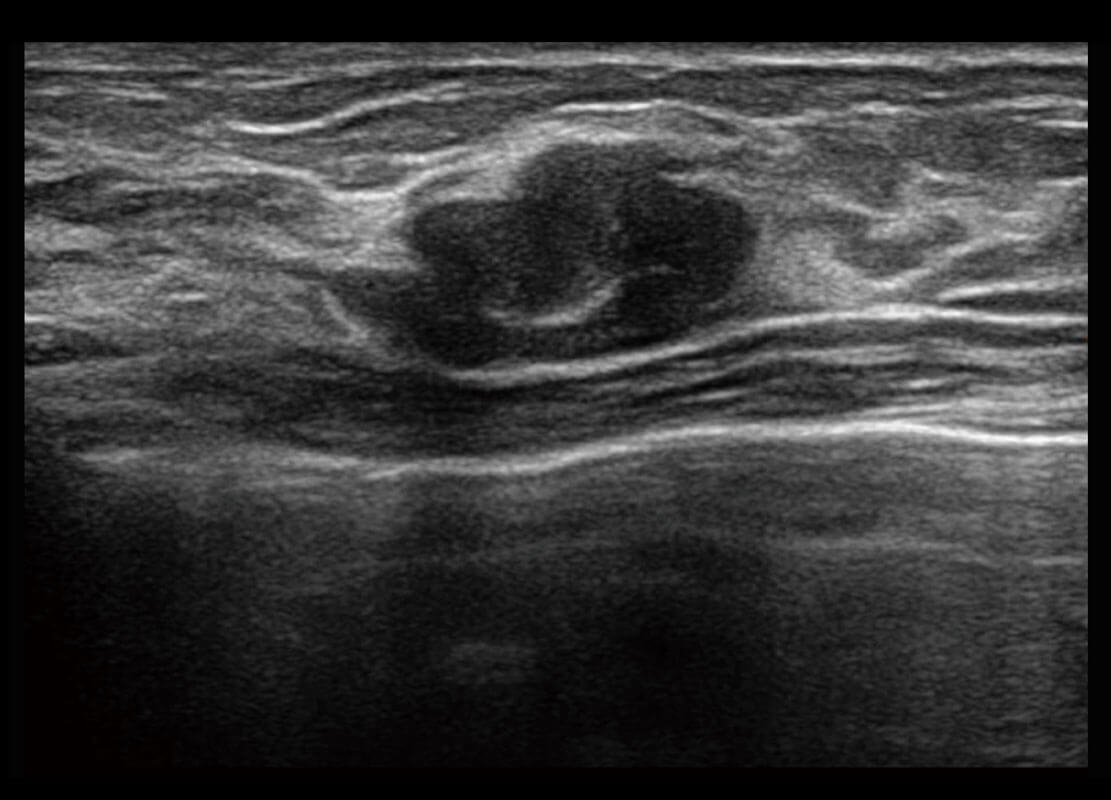

P60搭载宽频带线阵探头、宽景成像、弹性成像技术,为您提供乳腺应用方案。P60支持高频相控阵探头、线阵探头、腹部高频探头、腹部微凸探头等,丰富的探头群搭载敏感的彩色血流成像,适用于新生儿多种脏器检测要求,满足新生儿筛查需求。

乳腺导管癌

乳腺癌显微血流